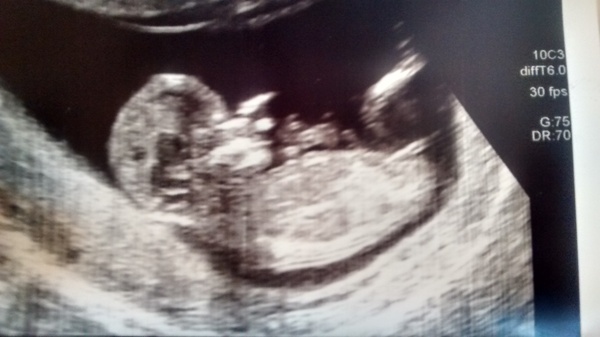

Hi all. I posted early on but have been patiently waiting my 12 week scan after a missed miscarriage at 12 weeks back in May. Over the moon to say all is well and due date 25th April. Such a relief and feel I can get excited about it all now. Second baby, have a 2 yr old boy already. It's been great to read all your stories and hope the next 6 months goes smoothly for us all.

Any nub guesses?

Northernlass congratulations! I'm sorry to hear about your mmc but so glad you're past 12 week safely this time!! Nub guess from me Would be a girl!